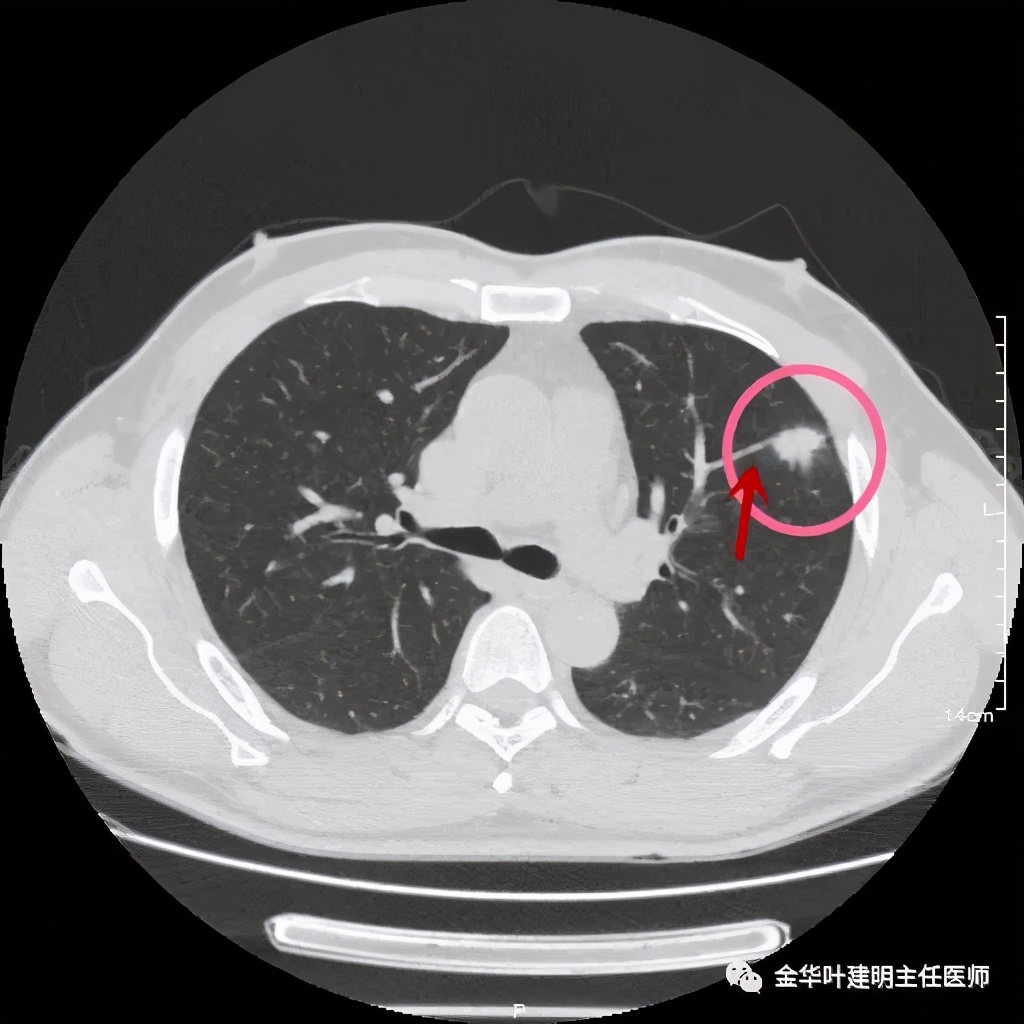

医生考虑炎性可能性大,予以头孢美唑抗炎治疗10来天,之后约一个月后复查了靶扫描,图像如下:

实性部分我看是有所缩小改善的,边上磨玻璃样的晕征更加明显了点

上图示病灶边缘向内凹陷,同时仍伴晕征

上图红色箭头示仍有血管进入,但蓝色箭头示边缘内凹,绿色示仍有晕征

上图红色箭头示血管进入病灶

医生告诉患者可以穿刺活检,也可予以胸腔镜下楔形切除。患者方选择手术切除。术后病理示:隐球菌感染伴肉芽肿性炎!